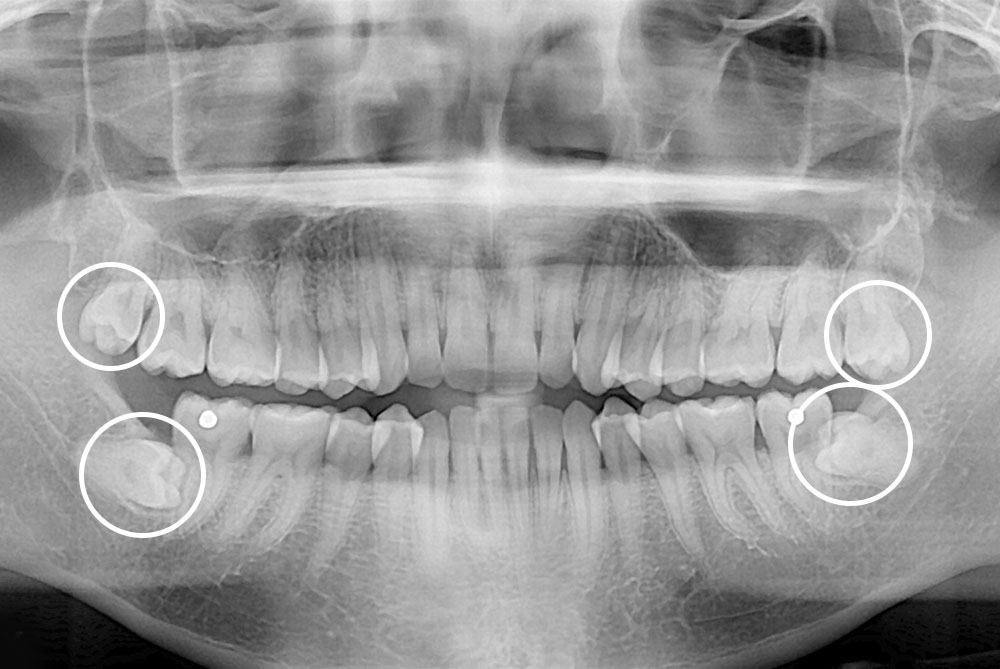

[사랑니] 매복 사랑니 발치

치료전 : 2018-08-09